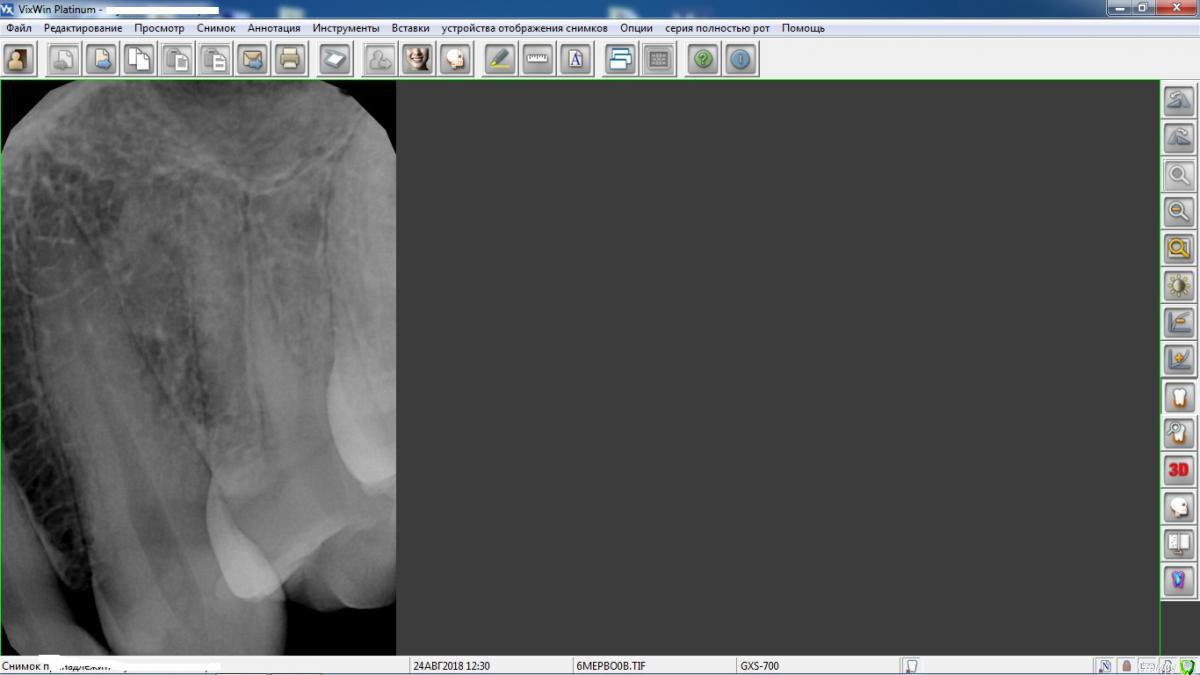

Venerika Опубликовано 25 августа, 2018 Поделиться Опубликовано 25 августа, 2018 Здравствуйте! делала плановые прицельные снимки. тк. часто бывает кариес на контактных поверхностях, которого не видно на обычном осмотре. на снимке клыка обнаружилось это. Терапевт заподозрил периодонтит, но не уверен. Помогите, разобраться? Визуально все в порядке, зуб ни на что не реагирует, не болит, не чешется - ничего. Буду благодарна за комментарии Ссылка на комментарий

kramer Опубликовано 25 августа, 2018 Поделиться Опубликовано 25 августа, 2018 норм все 1 Ссылка на комментарий

red_butler Опубликовано 25 августа, 2018 Поделиться Опубликовано 25 августа, 2018 норм все+1 Ссылка на комментарий